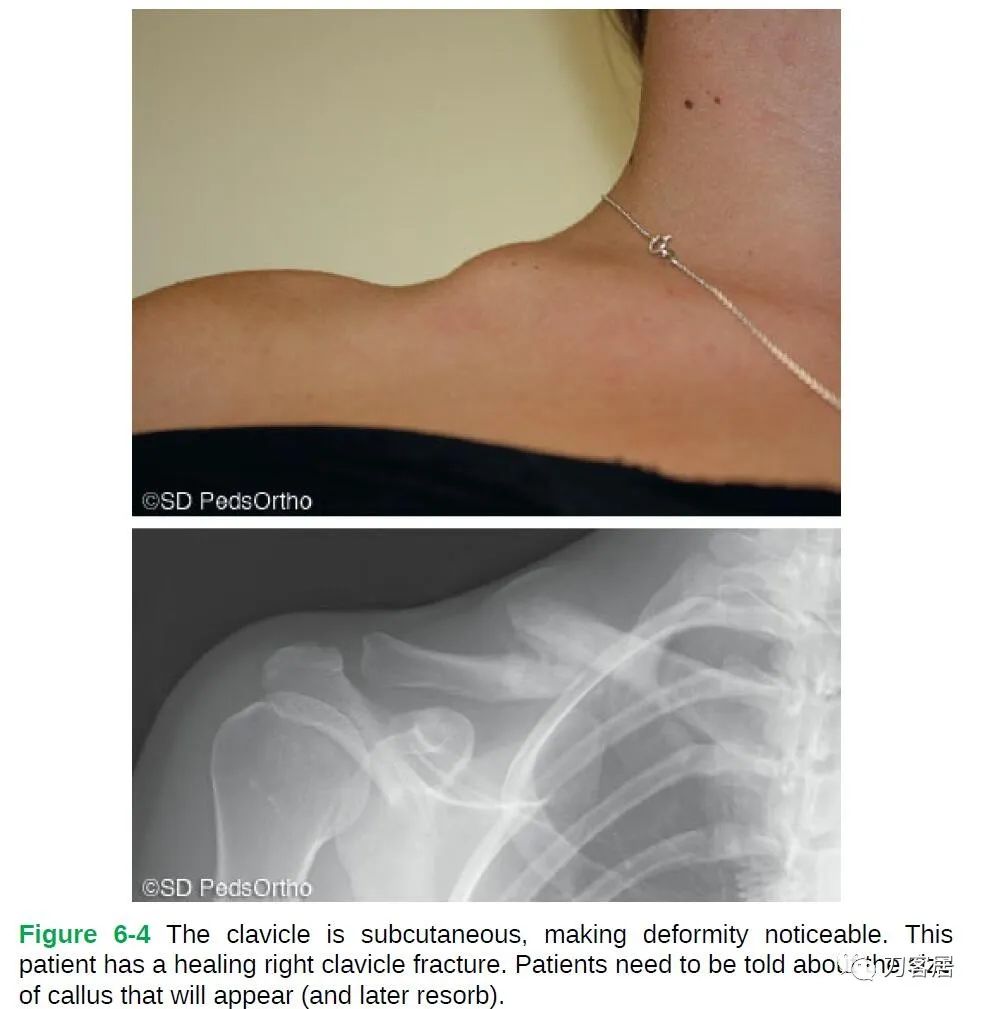

The examination of a child with a clavicle fracture is relatively straight forward given the superficial nature of the bone. Typically, the patient will present with the arm being held in an adducted position close to the body with the opposite hand supporting the injured extremity. The skin should be inspected for an open fracture or significant tenting (which has rarely been reported to erode through the skin). Typically, the clinical deformity, ecchymosis, swelling (Fig. 6-4), and point tenderness lead the physician to the diagnosis.

鉴于锁骨位置浅表,儿童锁骨骨折的检查相对直接。通常,患者会将手臂贴近身体置内收位,健侧手扶患侧上肢。应检查皮肤以判断有无开放性骨折或明显的局部隆起(很少有刺破皮肤的报道)。局部畸形、瘀斑、肿胀(图6-4)和压痛即可诊断锁骨骨折。

Figure 6-4 The clavicle is subcutaneous, making deformity noticeable. This patient has a healing right clavicle fracture. Patients need to be told about the size of callus that will appear (and later resorb). 图6-4 锁骨位皮下,因此畸形明显。此患者右侧锁骨骨折正在愈合。需告知患者将出现的骨痂大小(以及随后的再吸收)。